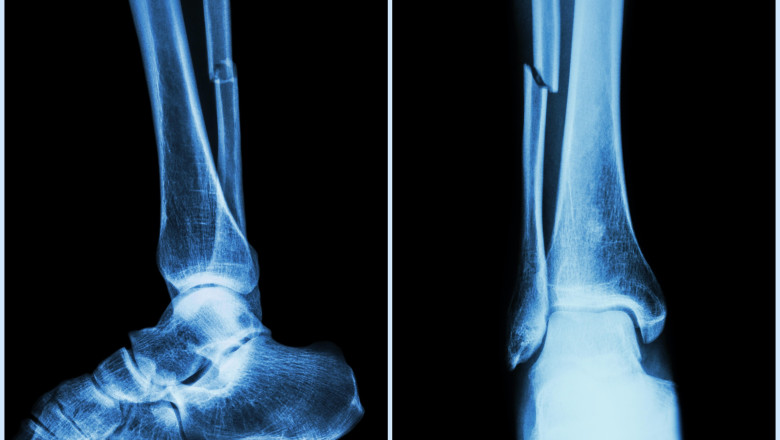

Cercetătorii chinezi din provincia Zhejiang au anunțat dezvoltarea unui adeziv osos inovator, capabil să repare fracturile și fragmentele osoase zdrobite în doar câteva minute. Noua substanță, denumită „Bone-02”, ar putea schimba complet tratamentele ortopedice tradiționale, reducând necesitatea intervențiilor chirurgicale invazive și a implanturilor metalice.

Forța de lipire a oaselor tratate cu „Bone-02” depășește 180 de kilograme, ceea ce îl face comparabil – sau chiar superior – implanturilor metalice tradiționale. Compoziția bazată pe calciu și proteine bioactive oferă o legătură puternică și flexibilă, care permite osului să se refacă fără complicații post-operatorii.

Metoda necesită doar o incizie minimă, prin care adezivul este introdus în zona fracturată, fixând și sigilând fragmentele osoase aproape instantaneu. Procedura durează mai puțin de trei minute, spre deosebire de tratamentele convenționale care pot dura ore întregi și implică plăci sau șuruburi metalice.